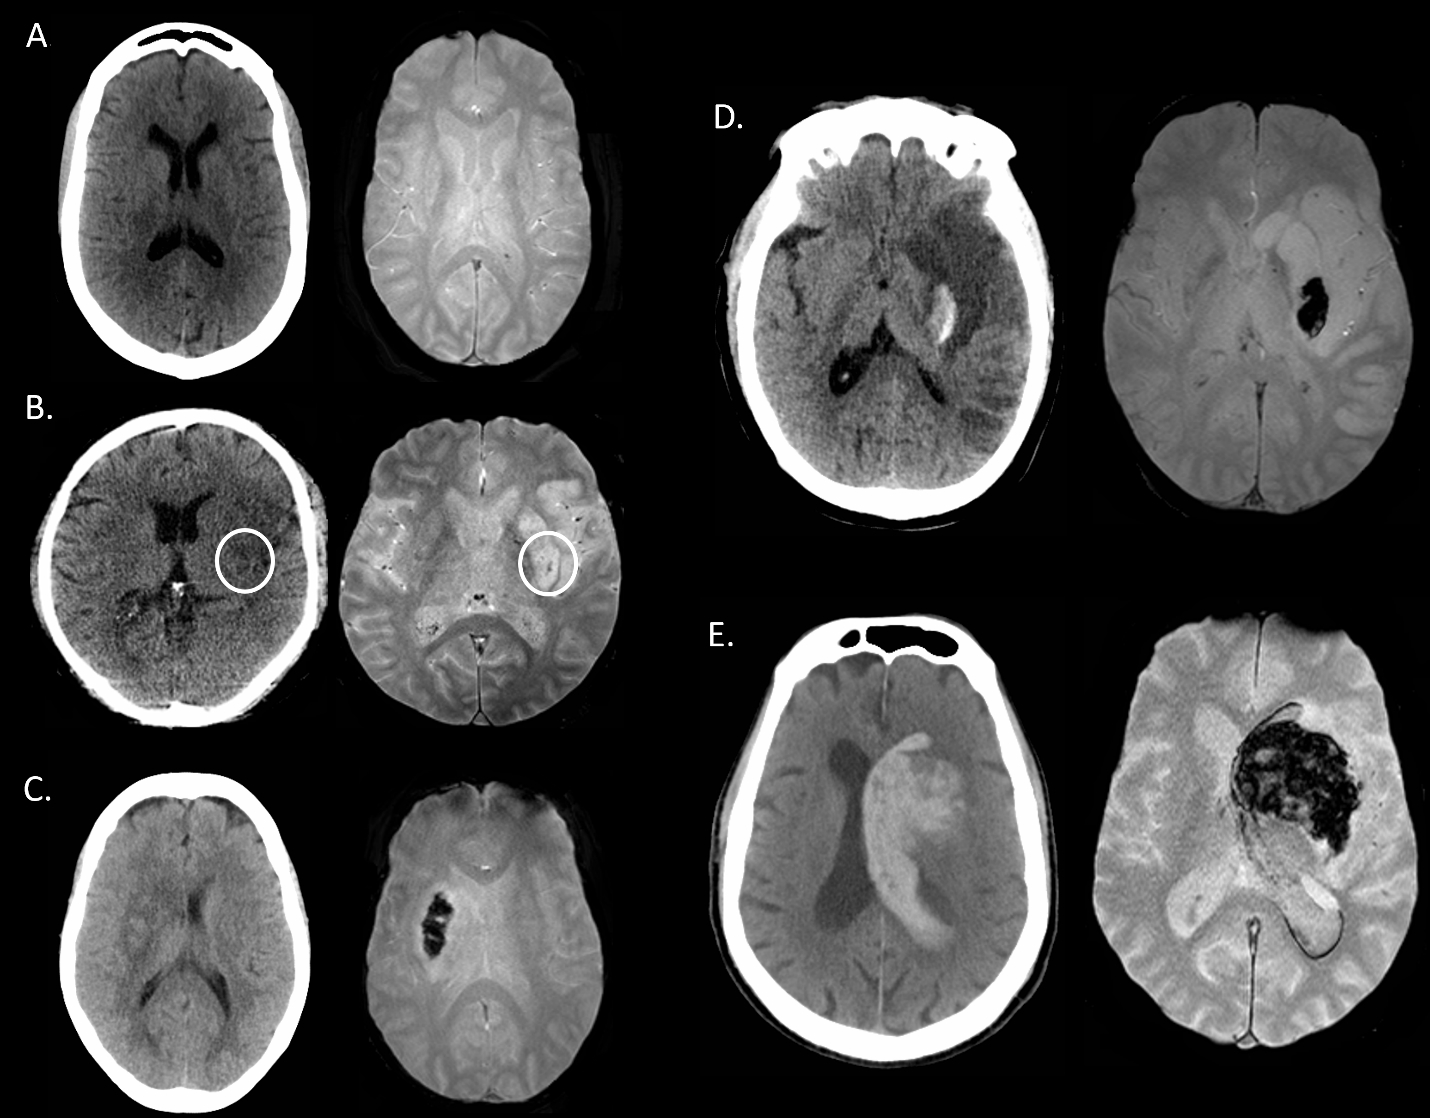

Comparison of HEmorrhage on CT versus MRI After ThrombEctomy: The HECATE study

The characterization of hemorrhage following acute stroke intervention has largely been CT-based. We sought to compare MRI- and CT-based scoring of hemorrhage after acute endovascular therapy (EVT) applying the Heidelberg Bleeding Classification (HBC) to assess inter-modal agreement and quantify inter-rater agreement.

Consecutive acute stroke patients were included in this retrospective study if they: i) had MRI and CT ≤12 hours of each other OR ii) had CT bracketed by MRI pre- and post-CT [i.e. MRI-CT-MRI] ≤7 days post-EVT. The concordance of the HBC ratings by consensus panel were compared between CT and T2*GRE MRI.

For the 87 EVT-treated patients included, median age was 68 years [60-74], admit NIHSS 18 [13-23], 47% were treated with IV/IA thrombolytics, and 93% were successfully recanalized (mTICI 2b/3). Hemorrhage was detected on at least one modality in 60% (52/87) of patients. We found a 68% (59/87, 95% CI [57-77%]) agreement overall between CT and MRI for hemorrhage classification post-EVT. MRI had the best inter-rater agreement for HBC 0 (no hemorrhage) with excellent concordance (κ=0.882), compared to CT (κ=0.683). T2*GRE MRI tended to have increased sensitivity to scattered petechial hemorrhage (HBC 1a) as compared to CT with 17% (2/12) inter-modal agreement. The inter-rater agreement of HBC class 2 (i.e. PH-2) was substantial for MRI (κ=0.781) and excellent in CT (κ=0.951), with 67% (8 /12) inter-modal agreement. SAH was detected in 24% (21/87) of patients on CT and/or MRI with 29% (6/21) inter-modal agreement.

With the exception of SAH and minor petechial hemorrhagic transformation, we found that MRI and CT are overall interchangeable for detecting and classifying hemorrhage after endovascular therapy, reassuring findings for both clinical-decision making and research application. Given the complexity of hemorrhage subtypes post-EVT, work to further refine a post-EVT hemorrhage classification scale with clinical correlation would be beneficial.